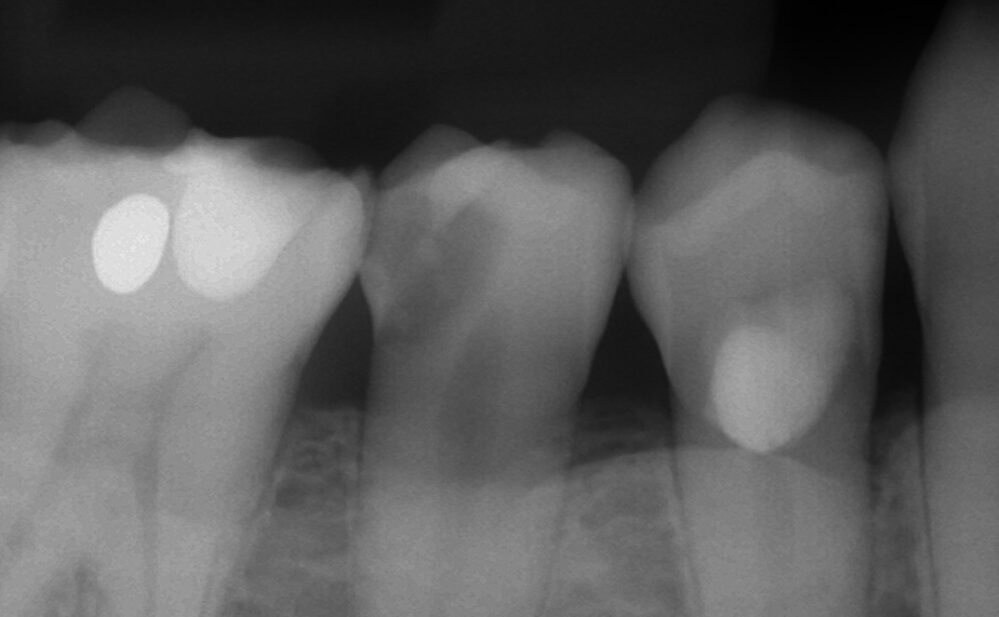

3年ぶりに歯科を受診、痛みはないがレントゲン写真検査にて小臼歯(奥歯)に神経に達する可能性のある程大きな虫歯が見つかりました。

通常の保険の虫歯治療でいくと、保険治療で神経を抜く治療を行いますので60〜70%の確率で根管治療は失敗し、歯を失う確率が高まります(東京医科歯科大学のデータより)

ご本人さまのご意向は、多少費用はかかっても良いので神経を保存したいとの事でしたので、8割の確率で神経を温存できるMTAセメントによる神経温存療法を試みることとなりました。